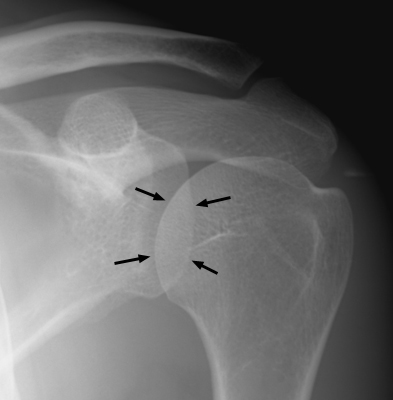

Diagnosis:Absent in posterior dislocation of the shoulder Discussion:Normal left shoulder x-ray (A) and second abnormal left shoulder x-ray (B) with posterior dislocation; notice the lack of overlap of the humeral head with the glenoid. Normally the medial part of the head of the humerus overlaps the glenoid fossa to form a shadow shaped like a half-moon which reaches down to the inferior border of the fossa. This disappears in posterior dislocation. References: